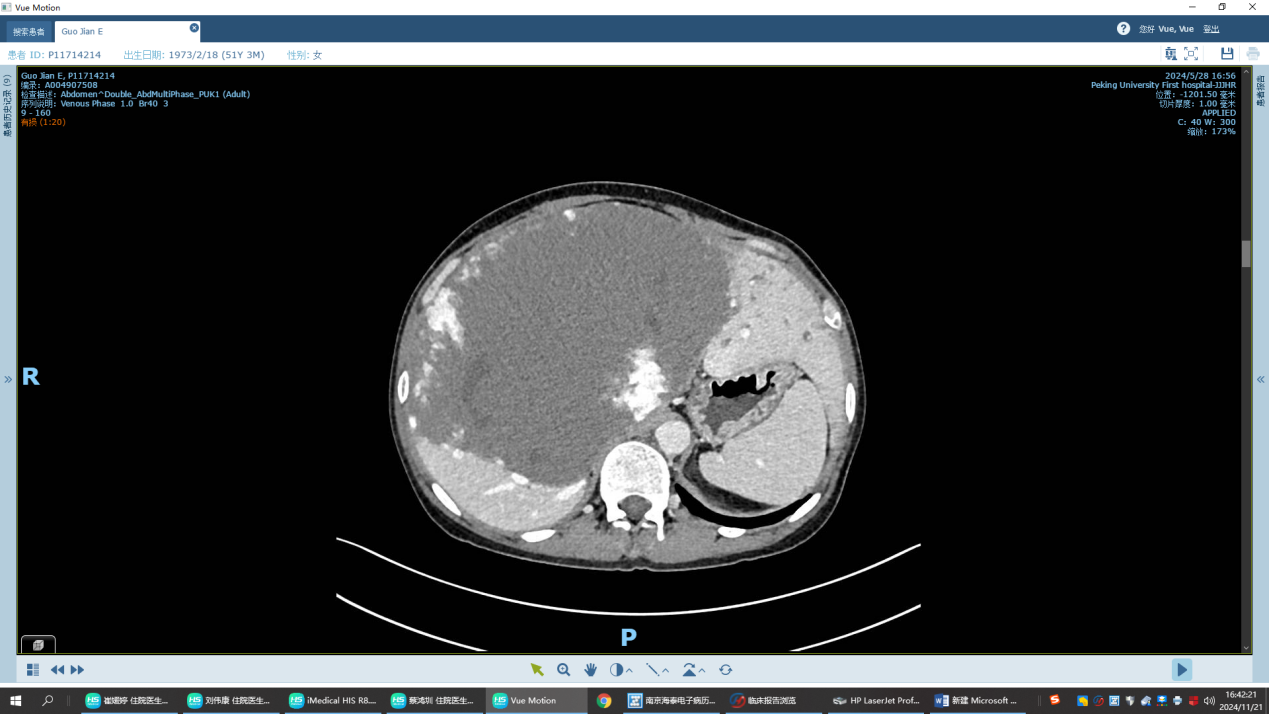

为什么会这样?是不是身体出了什么问题?患者一年前首诊于当地医院,腹部增强CT发现肝脏多发血管瘤,较大者约18.4*11.8cm。腹部增强核磁提示肝脏巨大占位,考虑肝海绵状血管瘤可能,余左右肝实质内见多发异常强化灶,考虑血管瘤伴异常灌注可能。

患者术前CT